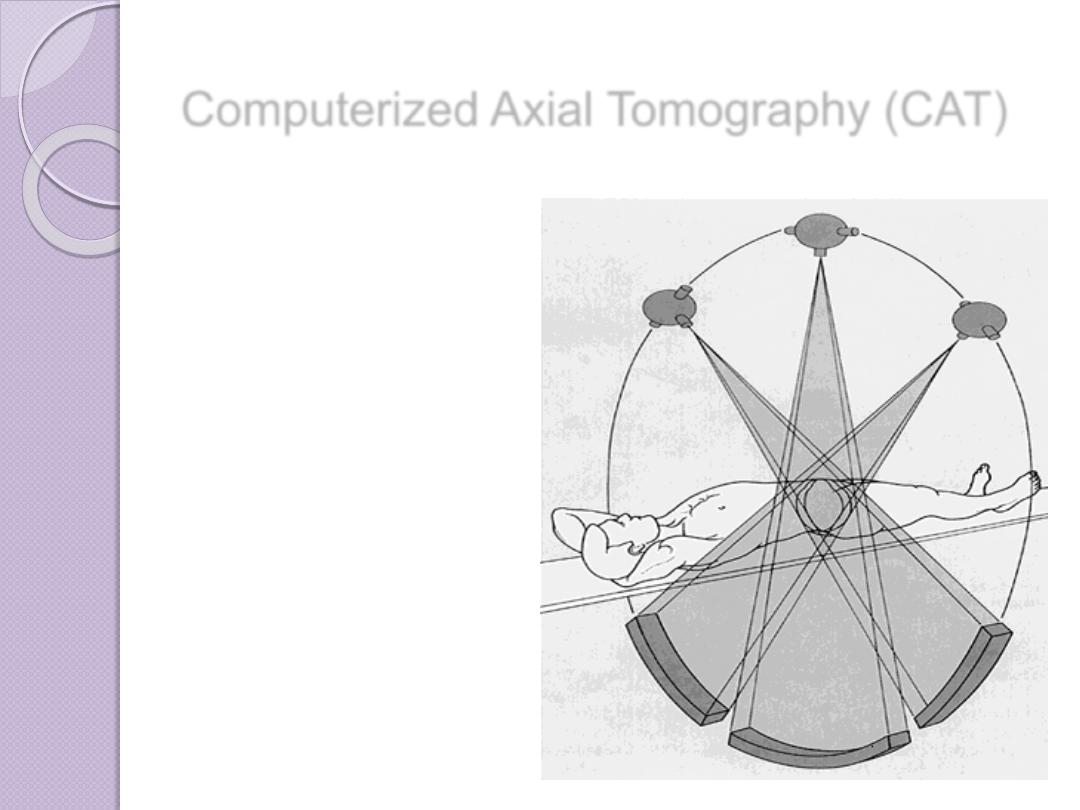

Computed Tomography

CT uses a computer to reconstruct mathematically a cross-

sectional image of the body from measurements of x-ray

transmission through thin slices of patient tissue. CT displays

each imaged slice separately, without the superimposition of

blurred structures that is seen with conventional

tomography. The x-ray beam is attenuated by absorption and

scatter as it passes through the patient. Sensitive detectors

on the opposite side of the patient measure x-ray

transmission through the slice. These measurements are

systematically repeated many times from different directi

ons

Computerized Axial Tomography (CAT)

In this process a small beam of x-

ray is passed through a plane of the

body while the x-ray tube moves in

an arc or a circle around the body

Computerized Axial Tomography (CAT)

The amount of radiation absorbed

by different elements of the chosen

plane varies according to X ray

absorptions by different tissues

Computerized Axial Tomography (CAT)

A computer stores a

large amount of data

from a selected region

of the body, making it

possible to determine

the spatial relationship

of the radiation-

absorbing structures

within it